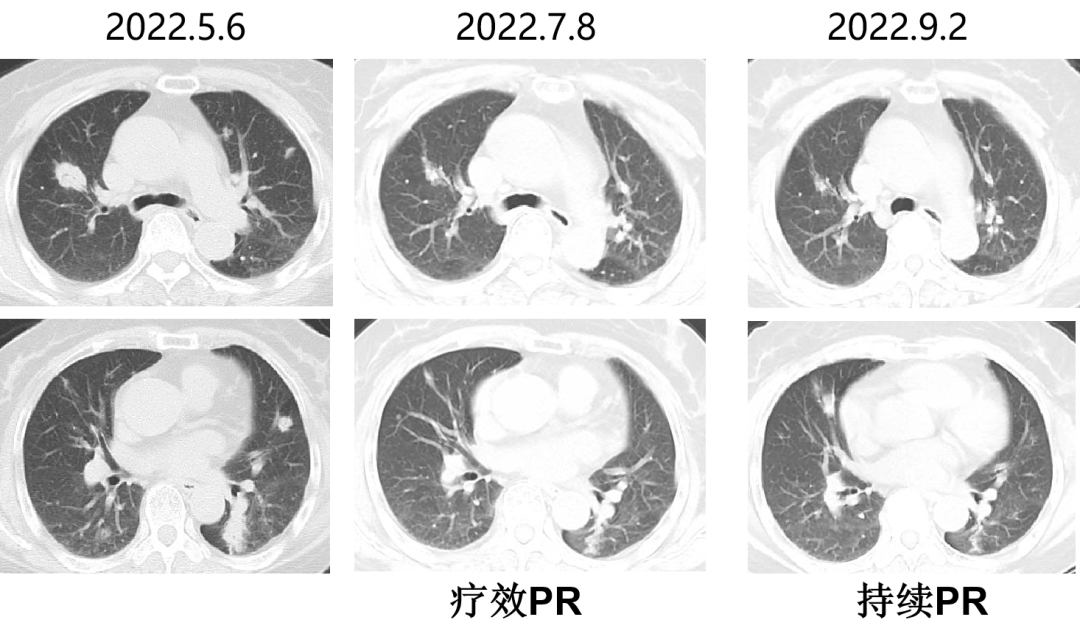

一 专家访谈 专家简介 于国华 教授 潍坊市人民医院 潍坊市肿瘤防治中心主任、潍坊市人民肿瘤医院院长、GCP机构副主任 潍坊市科技智库首席专家,省级重点学科负责人 中国临床肿瘤学会(CSCO)理事 山东省抗癌协会常务理事 潍坊市抗癌协会理事长 中国老年学学会舒缓治疗分会常务委员 中国老年学学会老年肿瘤专业委员会 中国老年学学会老年肿瘤专业委员会(CGOS)分子靶向分委会、肺癌分委会常务委员 山东省医学会肿瘤微创治疗分会副主任委员 山东省医学会姑息医学分会副主任委员 山东省肿瘤微创质量控制中心副主任委员 山东省医师协会肿瘤化疗医师分会副主任委员 山东省抗癌协会肿瘤化疗分会、肺癌分会、靶向治疗分会、心理治疗分会副主任委员 潍坊市医学会肿瘤化疗分会主任委员 潍坊市中西医结合学会肿瘤专业委员会主任委员 潍坊市肿瘤化疗专业质量控制中心主任 Q1 随着检查手段不断丰富,晚期结直肠癌的全程管理成为必然趋势。请您谈一谈我国在结直肠癌全程管理方面取得了哪些成果,未来应该朝着哪些方向努力? 我国在结直肠癌全程管理方面的进步成果,大概可以分为三个方面。 第一方面,随着医疗检测技术和诊疗理念的革新,我国早筛早治取得了良好进展。60~80年代我国检查技术相对落后,主要为粪便潜血试验展开有关肠道检查,而随着内镜技术的发展,肠镜检查逐渐普及,提高了结直肠癌早期患者的诊断率,推进了我国早诊早治的策略,使更多患者及早发现疾病并接受治疗。 第二方面,我国医疗制度具有优越性。随着我国全民医保的全面落实,“全民健康”理念的普及,就诊路径日益优化,更加快速便捷,使患者尽早获得诊断和治疗。 第三方面,国家癌症中心以及有关学协会的成立,推动了我国整体诊疗水平的不断提高。不仅为基层和各级医院搭建了良好的学习平台,推动了临床医生的再学习、再教育,也使得规范化诊疗、多学科协作(MDT)等优秀诊疗理念得以推广和实践。 第四方面,在内外科领域,药物治疗和手术治疗也是发展比较迅速。我国加速推进新药研发和医药服务创新,使更多药物尽快落地,惠及我国患者。相有关学协会积极组织形成了具有实践和指导意义的全程管理专家共识/指南,包括患者自身情况的评估、围手术期管理、治疗药物的选择、各线药物治疗方案、药物不良反应管理等。 关于结直肠癌全程管理未来的发展,需要以预防、规范化治疗和新药研发为抓手。 第一方面,预防是结直肠癌管理的第一步,未来有待在国家层面开展大规模的宣传教育,科普健康生活方式,令群众了解结直肠癌危险因素,从源头降低结直肠癌的患病风险。 第二方面,早筛早诊尽管已经取得显著成效,等仍需要深入基层,覆盖偏远贫困地区,使更多结直肠癌患者能够在早期发现,尽早干预,提升结直肠癌患者整体生存和预后。 第三方面,结直肠癌诊疗规范有待进一步提升,尤其需要在基层医疗单位加强规范化诊疗的理念。 第四方面,精准医学时代背景下,我们希望未来随着分子水平研究和精准医学研究的进展,在疗效监测和复发监测方面能使用更精准、更有价值的分子标志物动态监测。在手术前判断患者是否需要先做辅助化疗,在手术后判断是否需要进行复发监测,通过分子标志物可以更早地提示未来是否会复发,是否需要提前干预,如果复发,分子标志物可以再次作为监测指标指导治疗。 第五方面,我们还需加大研发力度,开发更多新机制、新靶点的药物,进一步提升晚期结直肠癌的疗效。 Q2 长期以来,化疗始终是肿瘤治疗领域的基石。其中,曲氟尿苷替匹嘧啶片(TAS-102)作为新型口服化疗药,问世以来不断为结直肠癌领域打开新的治疗格局,请您谈谈该药在中国的上市是基于怎样的研究成果? TAS-102在中国的获批是基于国际多中心 RECOURSE 研究和亚太TERRA研究的结果。RECOURSE研究是TAS-102的国际多中心Ⅲ期临床研究,显示TAS-102较安慰剂显著延长中位OS时间(7.1个月对比5.3个月)和中位PFS时间(2.0个月对比1.7个月),死亡风险和疾病进展风险分别降低32%和52%。此后,有众多中国临床专家参与的TERRA研究,证实了TAS-102在亚洲人群的安全性和有效性,TERRA研究重复出了RECOURCE研究的结果,TAS-102组患者的中位OS时间(7.8个月对比7.1个月)和PFS时间(2.0个月对比1.8个月)得到显著改善,死亡风险和疾病进展风险分别降低21%和57%。这两项关键研究成功改写了包括ESMO、NCCN、CSCO等中外权威指南的推荐。 而且,这两项研究中,TAS-102的不良反应均以血液学毒性为主,有症状的不良反应发生率低。鉴于其良好的安全性和耐受性,TAS-102与其他药物联合用于肠癌也在研究中进行了探索并取得了不错的结果。 Q3 晚期结直肠癌的发生通常预示着预后相对较差、患者生存期不长,但依然有治愈的可能,这关系到临床治疗用药方案的决策。今年上半年发布的CACA-RC指南推荐不适合强烈治疗患者应用TAS-102联合贝伐珠单抗,作为晚期不可切除结直肠癌姑息一线治疗方案。请您谈谈该推荐治疗对我国晚期不可切除结直肠癌的临床治疗产生了怎样的影响? 晚期转移性结直肠癌的标准化疗方案在指南中是以奥沙利铂或伊立替康为基础的FOLFOX和FOLFIRI方案,在此基础上,可以联合西妥昔单抗或贝伐珠单抗,但是,依旧有部分患者身体状况无法耐受加强化疗,少数患者因为高敏可能出现药物过敏,针对这一类患者,治疗方案的选择非常有限且预后情况并不理想。临床上往往推荐口服化疗药物+贝伐珠单抗方案。 2022年CACA-RC指南基于TASCO1研究的结果,推荐拒绝静脉化疗或不能耐受强烈治疗、易敏的晚期肠癌患者姑息一线选择TAS-102+贝伐珠单抗方案。TASCO1研究是一项旨在随机比较TAS-102+贝伐珠单抗和卡培他滨+贝伐珠单抗在一线治疗不可接受强烈治疗的不可切除转移性结直肠癌的Ⅱ期研究。研究结果显示:TAS-102组延长患者mPFS时间1.41个月(9.23个月对比7.82个月);延长患者mOS时间4.64个月(22.31个月对比17.67个月)。安全性分析也提示TAS-102+贝伐珠单抗治疗具有良好的耐受性,它最常发生的3/4级不良事件是中性粒细胞减少症。严重的发热性中性粒细胞减少症发生率约为4%。TAS-102+贝伐珠单抗方案因其高效、低毒的特点为不适合强烈治疗的转移性结直肠癌患者及老年患者带来了新的希望,其疗效与生存获益令人期待。 Q4 近年来,结直肠癌领域联合治疗的研究探索不断取得进步。请您谈谈,还有哪些研究进展为TAS-102联合贝伐珠单抗奠定一线治疗地位打下基础? 近年来,多项临床研究不断为TAS-102的临床可及性打下良好基础,DANISH研究将TAS-102与贝伐珠单抗联合用于转移性结直肠癌二线及以上治疗,发现联合组较TAS-102单药组疗效更好,中位PFS时间(4.6个月对比2.6个月)和OS时间(9.4个月对比6.7个月)显著延长,且联合组安全性可控,未出现非预期的不良反应。日本C-TASK-FORCE研究和欧洲DANISH研究均显示,对于PS为0~1分的转移性结直肠癌患者,TAS-102+贝伐珠单抗三线治疗实现了超过4.5个月的中位无进展生存期(PFS),超越了既往单药三线治疗的总体水平,且未显著增加不良事件(AEs)。TAS-102+贝伐珠单抗4周方案治疗转移性结直肠癌显示了良好的抗肿瘤活性。日本BiTS研究确证了双周方案可在不影响疗效的前提下,明显降低中性粒细胞减少症发生率。日本KSCC 1602研究和欧洲TASCO1研究都成功探索了FTD/TPI+贝伐珠单抗用于转移性结直肠癌一线治疗的疗效和安全性。 二 病例分享 专家简介 任海朋 主任 潍坊市人民医院 潍坊市人民医院肿瘤内科副主任,副主任医师 中国抗癌协会肿瘤微创治疗专业委员会委员 中国抗癌协会肿瘤消融治疗专业委员会委员 山东省健康管理协会消化道肿瘤防治分会副主任委员 山东省抗癌协会青年理事会常务理事 山东省医学会肝脏肿瘤多学科联合委员会委员 山东省抗癌协会消化道肿瘤分会委员 潍坊市医学会结直肠癌多学科联合专委会副主任委员 潍坊市医学会肿瘤微创治疗专业委员会副主任委员 潍坊市医师协会肿瘤化疗医师分会副主任委员 肖海凤 医师 潍坊市人民医院 潍坊市人民医院肿瘤内科主治医师,硕士 山东省抗癌协会化疗分会青年委员会委员 山东省疼痛医学会癌痛与姑息治疗专业委员会委员 山东省医学会科学普及分会肿瘤科普学组委员 山东省医学会精准医学分会消化道肿瘤学组委员 潍坊市医学会化疗专业委员会委员兼秘书 潍坊市抗癌协会乳腺癌专业委员会委员 潍坊市抗癌协会妇科肿瘤分会委员 潍坊市医学会第三届肛肠外科专业委员会青年学组委员 01 基本情况 基本情况:史xx,女,57岁,既往体健,无特殊病史,无家族史。 简要病史: 2020.1 患者出现大便带血,为暗红色,与大便相混,伴大便次数增多3~4次/天,大便不成形,伴肛门坠胀及里急后重感。 2020.4 就诊于潍坊市人民医院消化内科门诊,行肠镜示距肛门10cm环周隆起性病变,肠腔狭窄,镜身不能通过,考虑直肠癌,活检病理示腺癌(中分化)。 2020.4.16 就诊于我院肛肠外科一区,行胸腹盆部CT提示乙状结肠占位,考虑肿瘤,盆腔肿大淋巴结,双肺多发转移瘤。 诊断:直肠癌(cT3N+M1a,IVa期)。 2020.4.18 肺多发转移(CT) 2020.4.18 直肠原发灶(CT) 2020.5.12 基因检测 KRAS:Exon2、Exon3无突变;NRAS:Exon2、Exon3 无突变;BRAF:Exon15(V600E)无突变。UGT1A1*28:TA6/7,UGT1A1*6:G/G。MSS。 02 治疗经过 因直肠原发灶进镜困难,肠腔狭窄,发生肠梗阻风险较大,建议先行原发灶切除,后行全身抗肿瘤治疗。 2020.4.23 行直肠癌根治术(前切除术)+回肠预防性造口术+肠粘连松解术。 术后病理 一线治疗经过 2020.5.18至2021.1.31 行奥沙利铂甘露醇注射液225mg d1+卡培他滨1.5g bid d1-14方案化疗8周期。 不良反应:胃肠道反应不著,骨髓抑制最重2度。 疗效评价:5周期后疗效评价为PR,8周期后疗效评价为PD。 双肺转移灶(一线) 二线治疗经过 入住我科,ECOG 0分,身高159cm,体重65kg,体表面积1.64m2。 2021.3.9、2021.3.29、2021.4.12、2021.5.6、2021.5.25、2021.6.21、2021.7.9、2021.7.28、2021.8.15行西妥昔单抗800mg d1+伊立替康300mg d2+氟尿嘧啶650mg iv,4000mg civ 46h+左亚叶酸钙325mg d2化疗9周期。 不良反应:胃肠道反应不著,骨髓抑制2度。 疗效评价:缩小的SD。 双肺转移灶(二线) 三线治疗经过 2021.9至2022.5.6 口服呋喹替尼5mg qd d1-21 q28d治疗。 不良反应:高血压病1级,轻度肝功损伤。 疗效评价:2个月后疗效评价PR,7个月后肺内病灶增大,肝内出现新发病灶,疗效评价PD。 双肺转移灶(三线) 肝脏(新发病灶) 四线治疗经过 2022.5至今 开始应用贝伐珠单抗300mg d1联合TAS-102 55mg bid d1-5双周治疗。 不良反应:高血压2级,继发性甲状腺功能减退,白细胞减少I度,中性粒细胞减少2度,贫血1级。 疗效评价:PR。 03 病例小结 04 心得体会 TAS-102是一种新型口服细胞毒药物,是口服的氟尿嘧啶类药物,作用机制不同于氟尿嘧啶,可用于氟尿嘧啶耐药患者。 国际RECORSE和亚太TERRA研究证实,TAS-102在mCRC治疗中具有一致的疗效和安全性:1.显著延长mCRC患者生存期,降低死亡和疾病进展风险,尤其对于≥65岁患者获益更显著;2.显著延缓体能下降,为持续治疗提供体能储备;3.主要不良事件为血液学毒性。 双周TAS-102联合贝伐单抗不仅不降低疗效,而且明显降低中性粒细胞减少症发生率。 *本文仅代表专家观点,并经专家审校。